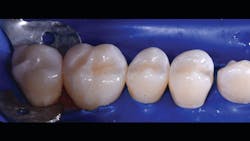

The final piece of the puzzle is the composite materials. In this case, Filtek One Bulk Fill Restorative (3M) and Filtek Bulk Fill Flowable Restorative (3M) were used. Bulk filling is more time efficient, technically simpler, and creates a monolithic form. Manipulation of composites and layering is known for a higher incidence of voids and defects. This case demonstrates the method of injection molding, which has the ability to create strong, monolithic, void-free, ideally contoured, mirror-finish restorations. Significant time savings occurs with simpler finishing requirements. Excess composite at the mid buccal, lingual, and occlusal areas is quickly reshaped with a disc. The subgingival area is then finished with a finishing strip. Finally, it’s time to finish and polish using a diamond-impregnated rubber polisher.

In the following case study (figures 1–11), the techniques and methods discussed will be demonstrated with the treatment of a quadrant of four posterior restorations. Four interproximal smooth-surface carious lesions are conservatively treated with two nonretentive saucer preparations and two marginal ridge-preserving opportunistic preparations.